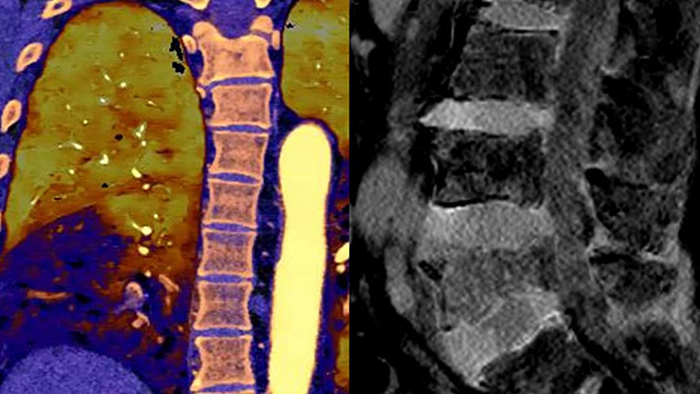

CT-Systeme mit Spektraldetektor machten konventionelles CT zu quantitativem CT. Die zweite Generation des Philips Spectral CT 7500 erhielt den Aunt Minnie Award for Best New Radiology Device in 2021.

Im Gegensatz zur klassischen CT-Untersuchung beinhalten Spektraldetektor-CT-Daten immer auch spektrale Informationen, ohne spezielle Vorkehrungen oder zusätzliche Vorbereitungen. Das bedeutet, Sie können die Spektraldaten jeder Untersuchung auch retrospektiv mit unterschiedlichen Diagnosetools analysieren. Sie können beispielsweise die monoenergetischen Energielevel anpassen oder Z-effektive Bilder erhalten.

Der Spektraldetektor absorbiert und differenziert gleichzeitig die hohe und niedrige Energie eines einzigen polyenergetischen Röntgenstrahls. Spektralergebnisse werden in einem einzigen Scan ohne Einstellung separater Scan-Modi erfasst.

Spektralergebnisse – jederzeit und überall. Eine einzelne DICOM-Entität enthält ausreichende Informationen für die retrospektive Analyse.

Ein CT-System mit Spektraldetektor absorbiert und differenziert gleichzeitig die hohe und niedrige Energie eines einzigen polyenergetischen Röntgenstrahls auf Detektorebene.